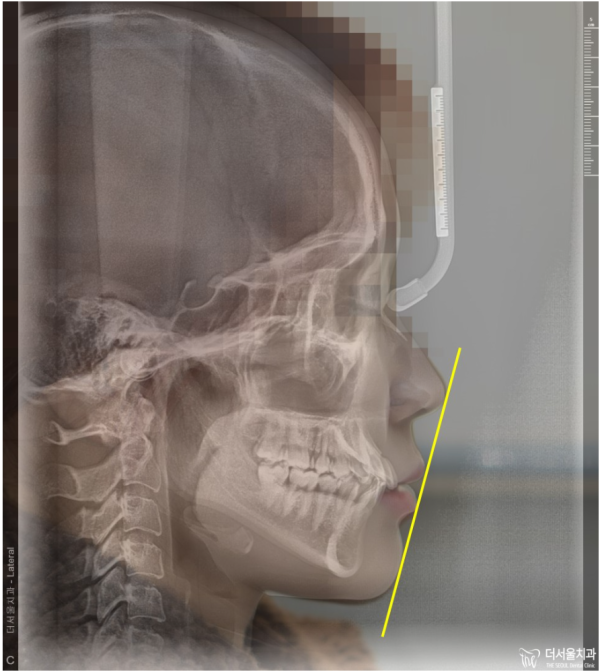

이분같은 경우는 리케츠라인으로 돌출입을 확인해보아도 일직선을 크게

벗어나지 않는 형태를 보이고 있습니다.

하지만 앞니가 뻐드러져 있는 것을 확인할 수 있죠?

like this one has a straight line even if you check the protrusion with a Liketz line.

It's a form that doesn't deviate.

But you can see that the front teeth are sticking out, right?